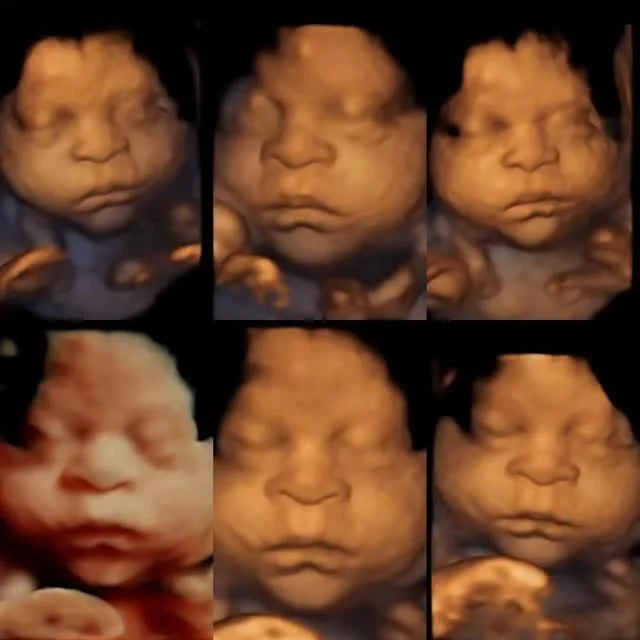

With the start of the New Year I decided to expand an idea a friend had started for me. I wanted to be able to offer speciality baby items. From the ever priceless Heartbeat Animals to themed onesies and baby shower ideas and gifts. I want to be able to be a one stop shop. Who doesn't want to find out the gender of their baby, walk a few feet back to the front and pick out the perfect exciting item to announce it with?! Our confetti cannons and confetti push pops are flying off the shelves and we are so happy about this! Finding out the gender of your baby is a wonderful, exciting and life changing event that we want to help everyone enjoy that much more. Friends? Family? Bring them with you! Don't want to know today?! We will seal it in a special envelope and can even wrap up the secret cannon of your baby's gender to find out later. We do it all! Or I do should I say I do it all.